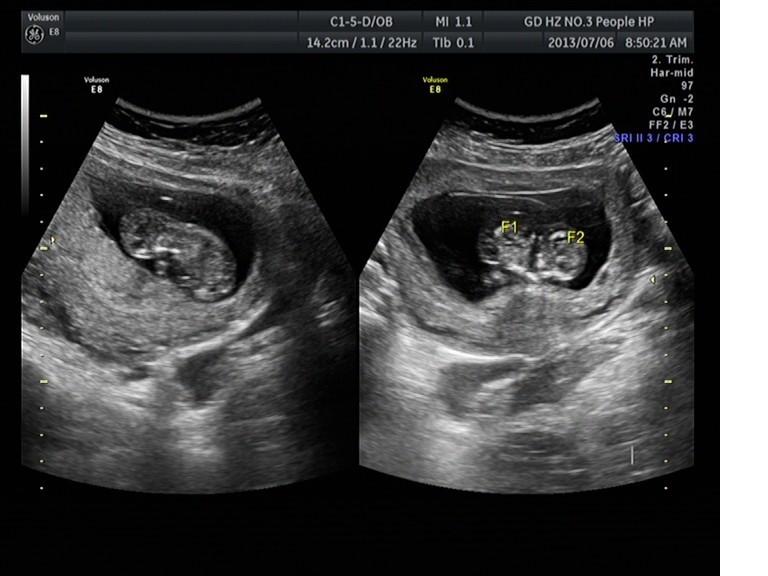

随着环境污染日益严重,随着各种地沟油的诞生,随着各样镉大米的泛滥……我们的健康越来越受到威胁,很多疾病也随之接踵而至,胎儿先天性疾病也越来越多见。7月6日,我院超声科王瑶医生在做胎儿产前NT筛查中发现一例孕约11周+的联体双胎。超声所见:增大的子宫内可见联体双胎儿回声,可见两个胎头不能分离,胸部及腹部融合,可见一个增大的心脏。

联体婴儿B超图像